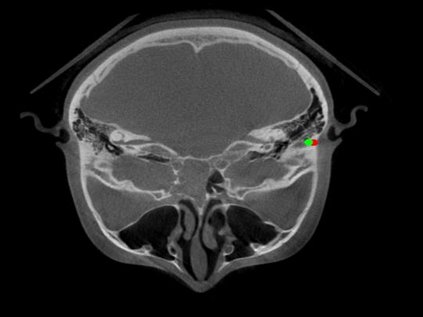

Detecting 3D landmarks on cone-beam computed tomography (CBCT) is crucial to assessing and quantifying the anatomical abnormalities in 3D cephalometric analysis. However, the current methods are time-consuming and suffer from large biases in landmark localization, leading to unreliable diagnosis results. In this work, we propose a novel Structure-Aware Long Short-Term Memory framework (SA-LSTM) for efficient and accurate 3D landmark detection. To reduce the computational burden, SA-LSTM is designed in two stages. It first locates the coarse landmarks via heatmap regression on a down-sampled CBCT volume and then progressively refines landmarks by attentive offset regression using multi-resolution cropped patches. To boost accuracy, SA-LSTM captures global-local dependence among the cropping patches via self-attention. Specifically, a novel graph attention module implicitly encodes the landmark's global structure to rationalize the predicted position. Moreover, a novel attention-gated module recursively filters irrelevant local features and maintains high-confident local predictions for aggregating the final result. Experiments conducted on an in-house dataset and a public dataset show that our method outperforms state-of-the-art methods, achieving 1.64 mm and 2.37 mm average errors, respectively. Furthermore, our method is very efficient, taking only 0.5 seconds for inferring the whole CBCT volume of resolution 768$\times$768$\times$576.